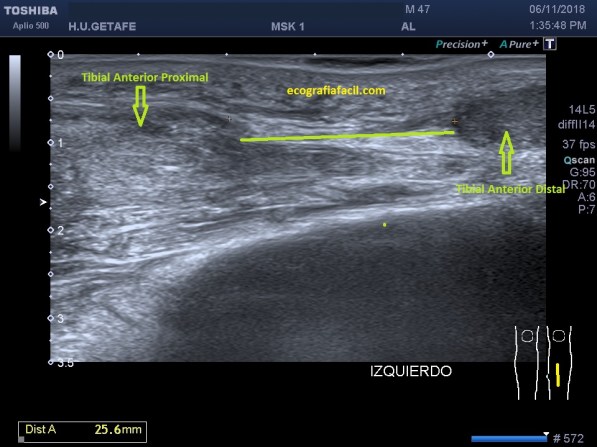

¿Cómo se vive ecográficamente este escenario? Los dos cabos del tendón se separan y se retraen, se vuelven hipoecogénicos, grandes y entre ellos existe un espacio que estará ocupado por derrame, grasa y además un efecto de «perdida de contorno» en la piel.

En las imágenes superiores y como si fuesen fotogramas ves:

- Cabo proximal del tibial anterior en corte longitudinal.

- Separación de ambos cabos tendinosos con medida, muy importante para planear una posible cirugía.